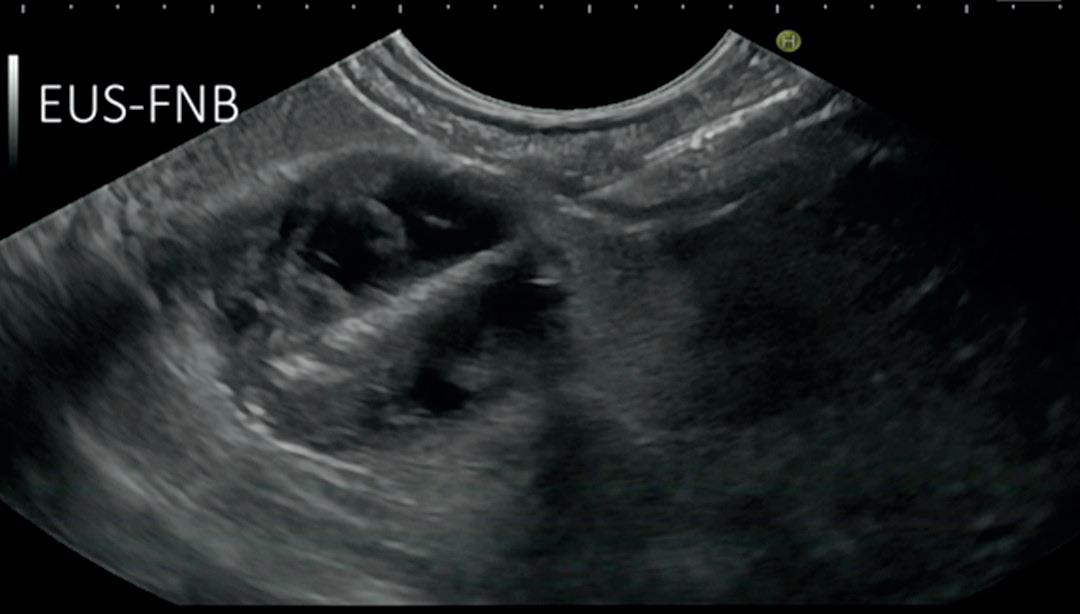

Fra billeddiagnostikk til vevsprøver og intervensjoner

I de første tiårene var ren avbildning med vevskarakteristikk av svulster og lymfeknuter ved hjelp av UL-bildet i seg selv, og etter hvert med støtte fra ulike billedmetoder som fargedoppler, det mest aktuelle. På 1990-tallet ble skop med lineær skanning tilgjengelige, som ga muligheten til direkte visualisering i sanntid av finnålsaspirasjon (FNA) til cytologisk vurdering (figur 2) (1). Ut over 2000-tallet ble EUS-FNA teknikken stadig mer utbredt i diagnostikk og stadievurdering av cancer, vurdering av lesjoner i pankreas, og subepiteliale lesjoner i GI-traktus. UL-teknologien har også utviklet seg betydelig, slik at billedkvalitet, fargedoppler, kontrastforsterket EUS og elastografi kan benyttes med EUS skop og bidra til vevskarakterisering. Imidlertid er det oftest slik at “tissue is the issue”. Derfor har utviklingen av bedre EUS-biopsinåler vært av stor betydning for undersøkelsens plass som en del av bl.a. pakkeforløp ved mistanke om cancer i pankreas, ved utredning av intramurale svulster, samt til påvisning av metastaser i lymfeknuter eller venstre binyre. I de senere årene har de såkalte 2. generasjons biopsinålene vunnet frem som de mest effektive nålene. Spissen av nålen har ofte en sliping i en “krone”- eller “gaffelform”, som gir en skarp nål med sylinderbiopsier fra målorganet. De mest benyttede nålene har en diameter på 22 G som er en knapp millimeter, men man kan også benytte tykkere nåler på 19 G eller tynne nåler ned til 25 G. Best dokumentasjon har disse

A: Lineært EUS skop med ultralydplanet i forlengelsen av endoskopets instrumentkanal. Instrumenter som føres gjennom arbeidskanalen vil derfor være synlig i sanntid på ultralydbildet samtidig som de er synlige idet endoskopiske bildet. B: EUS veiledet biopsi (EUS-FNB) med biopsinålen i UL planet fra høyre side i bildet. Biopsi av en semicystisk lesjon i pankreas (Bilde R.F. Havre)